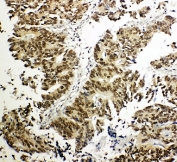

IHC-P: NRF1 antibody testing of human intestinal cancer tissue